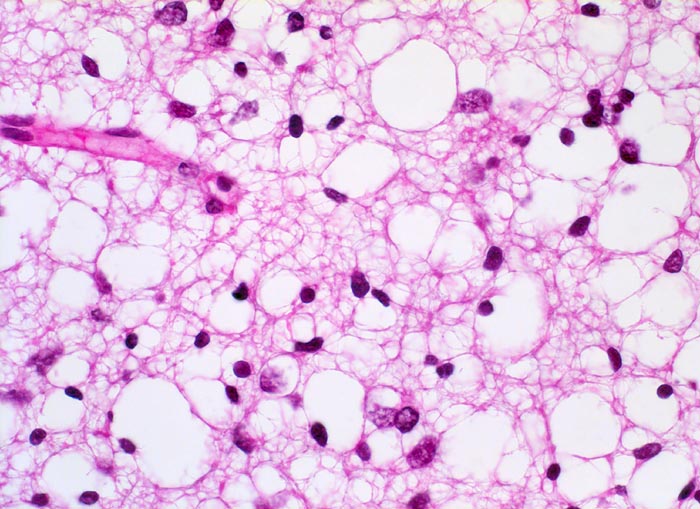

Histologisch bestehen die Oligodendrogliome aus kompakten Aggregaten runder Zellen mit deutlichen Zellgrenzen und klarem Zytoplasmasaum um einen dichten runden zentralen Kern (“Spiegelei”). Die Vakuolisierung des Zytoplasma stellt einen Fixationsartefakt dar und fällt bei Schnellschnitten als diagnostisches Hilfsmittel weg (Gefrierschnitt!). Charakteristisch sind verzweigte Kapillaren. Die Tumorzellen infiltrieren die Hirnrinde diffus und können sich bis in die Meningen ausbreiten.

• Fokale mukoide/zystische Degeneration innerhalb des Tumors mit Ausbildung von Pseudozysten.

• Dichtes Netzwerk verzweigender Kapillaren.

• Tumorzellen umgeben von einem Halo ("Spiegeleier").

• Die Tumorzellen erinnern an Oligodendrozyten der weissen Substanz, haben aber deutlich grössere Kerne.

• Im Gegensatz zum Glioblastoma multiforme monomorphes Zellbild.